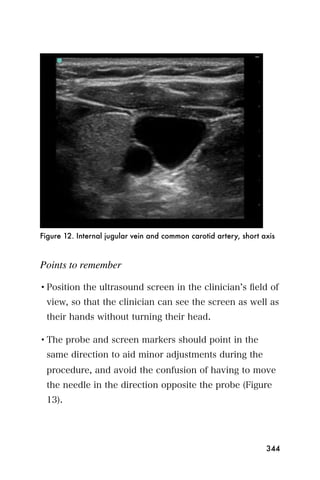

not reflect acute disease. In areas where tropical

splenomegaly is common, the implications of splenic

206

enlargement may be unclear, though an acute increase

in spleen size may be more useful. A more specific

condition called idiopathic tropical splenomegaly is a

defined by a combination of:

• splenomegaly

• elevated IgM levels